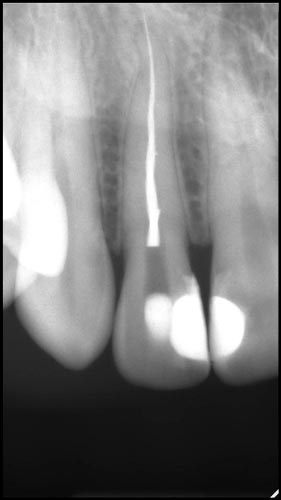

Погляд на сепаровані інструменти. Статистика поломок. Вплив на успішність ендодонтичного лікування. Протокол ухвалення рішення про вилучення уламка. Процедура вилучення за допомогою ультразвуку та альтернативні методики (Ендо ковбой, Петля Тераучі, система Кантервіль, ІРС.). Супутні ускладнення під час вилучення уламків. Мініінвазивна техніка вилучення.

• Що робити при неможливості вилучення?